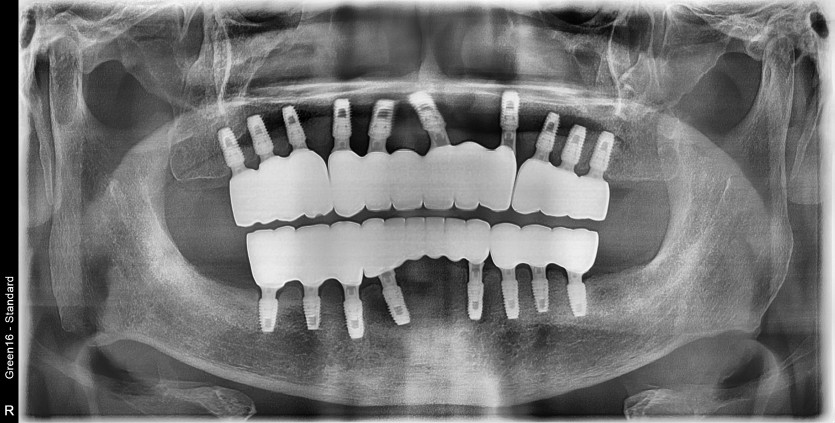

만 65세 전체 임플란트 증례

전체 임플란트 증례입니다.

18개의 임플란트로 완성하였습니다.